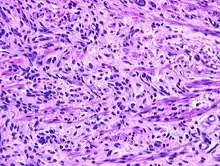

A hematoxylin and eosin stained image (high power) of the short spindle cells of a fetal rhabdomyoma.

Fetal rhabdomyoma are separated into two histologic types: Myxoid and cellular.[7][8] However, irrespective of histologic type, these tumors almost never show necrosis or increased mitoses. However, a cambium layer, abnormal mitoses and nuclear pleomorphism is not seen.

Cellular fetal rhabdomyomas are composed of bland, primitive spindled cells. The spindle cells are haphazardly arranged primitive, elongated skeletal muscle cells. The cells are set within a well-developed fibromyxoid stroma. A different pattern (intermediate type) is predominantly composed of cells with better differentiation towards skeletal muscle. There are often large ganglion cell-like rhabdomyoblasts showing prominent nucleoli within nuclei that show vesicular chromatin distribution. Another population includes strap-like rhabdomyoblasts with darkly staining pink cytoplasm. Nearly all tumors show short to more sweeping fascicles of spindled rhabdomyoblasts. The tumor cells may infiltrate into adjacent skeletal muscle or fat. It is not uncommon to see peri-neural association, although not perineural infiltration.[9]